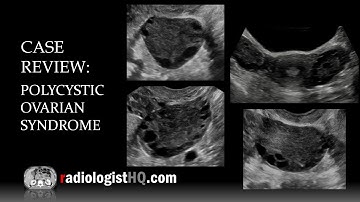

Noise Reduction Using OBNLM Filter and Deep Learning for Polycystic Ovary Syndrome in Matlab